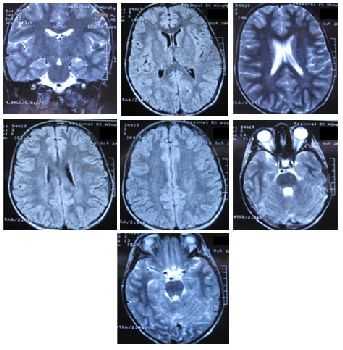

УЗИ головного мозга в большинстве случаев проводится для тех детей, которые появились на свет раньше срока, а также находятся в слабом состоянии. Если малыша пришлось реанимировать, тогда ему тоже назначают нейросонографию. Чуть реже могут использовать КТ и МРТ, потому как данные процедуры всё же рекомендуется проводить детям, которым уже больше трёх лет.

Чтобы диагностировать и выявить кисту у новорожденного в голове, специалист назначает МРТ, УЗИ или КТ головного мозга. Прогноз, который даст врач, будет зависеть от размеров и расположения.

Нейросонография. Голову ребёнка исследуют с помощью ультразвука. Он позволяет выявить незначительные отклонения в головном мозге новорожденного. УЗИ эффективно и безболезненно, передаёт полную картину состояния нервной системы. Обычно проводится через большой родничок сразу после рождения при наличии отклонений со стороны реакций малыша.

МРТ. Магнитно-резонансное исследование показано новорожденным, если УЗИ не даёт достоверной информации, а отклонения со стороны центральной нервной системы ярко выражены. При прогрессии болезни МРТ проводится в регулярном порядке.

Новорожденным со сходной клинической симптоматикой проводят комплексное обследование, которое состоит из осмотра нейрохирургом и УЗИ головного мозга. Мониторинг детей, страдающих кистой головного мозга, заключается в регулярном проведении ультразвуковой диагностики, а в тяжелом случае – МРТ.

Кистозные образования в головном мозге у младенцев обнаруживают при помощи нейросонографии. Это ультразвуковое абсолютно безвредное исследование головного мозга. Первую диагностику проводят до рождения. А затем в возрасте одного месяца.

Позже диагностика проводится в три месяца, затем в полгодика, год. В этом возрасте уже производится магнитно-резонансная и компьютерная томография.

Лечение кисты зависит от ее вида, месторасположения, размеров и формы, а также с интенсивностью ее динамики. Единое правило для всех: диагностика кисты головного мозга у грудничка подразумевает постоянный контроль за малышом. Это не только проведение УЗИ и МРТ и РТ, но и наблюдение за поведением ребенка, отклонениями в развитии:

Присутствие кисты головного мозга у новорожденных до года легко определяют с помощью ультразвукового исследования, которое проводят всем детям в течение первого месяца жизни. Это самое подходящее время для проведения процедуры, ведь родничок не зарос полностью и кости черепа не сомкнулись. В первую очередь, УЗИ головного мозга необходимо недоношенным детям. Целесообразно проведение УЗИ у новорожденного, если ему по каким-нибудь причинам необходима интенсивная терапия или сразу после рождения проводились реанимационные мероприятия.

Диагностировать наличие аномалии в головном мозге у ребенка позволяет ультразвуковое исследование — нейросонография .

Провести ее возможно только до достижения ребенком годовалого возраста, пока большой родничок на головке младенца не закрылся.

В более поздние сроки такое обследование не имеет смысла.

Для детей старше года для обследования на наличие кисты головного мозга рекомендуется МРТ (магнитно-резонансная томография).